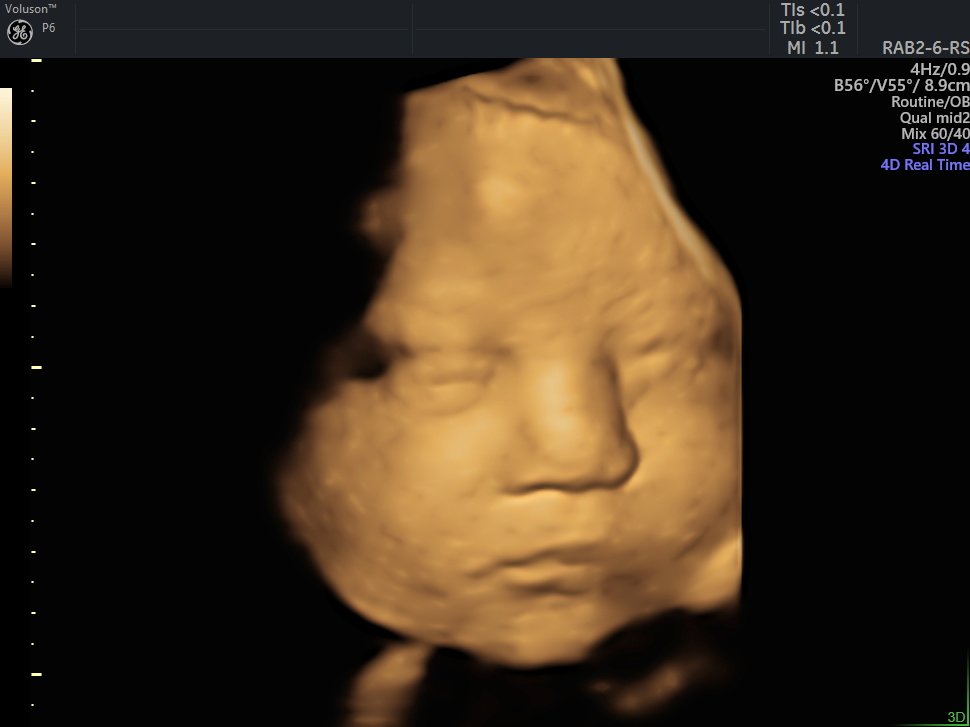

4 D Ultrasonografi

4 Boyutlu (Renkli) Ultrason ve Doppler Ultrasonografi